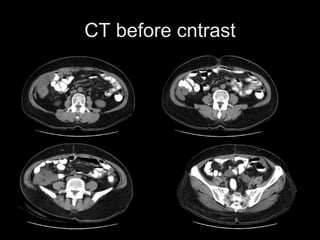

Pseudomyxoma peritonei (PMP) is a rare condition characterized by gelatinous ascites resulting from the rupture of appendiceal mucinous tumors, leading to significant abdominal complications. The incidence is approximately 2 cases per million per year, with a predominance in females, and diagnosis often relies on imaging techniques like ultrasound and CT scans. Effective treatment involves cytoreductive surgery combined with hyperthermic intraperitoneal chemotherapy (HIPEC) to manage disease progression and improve outcomes.